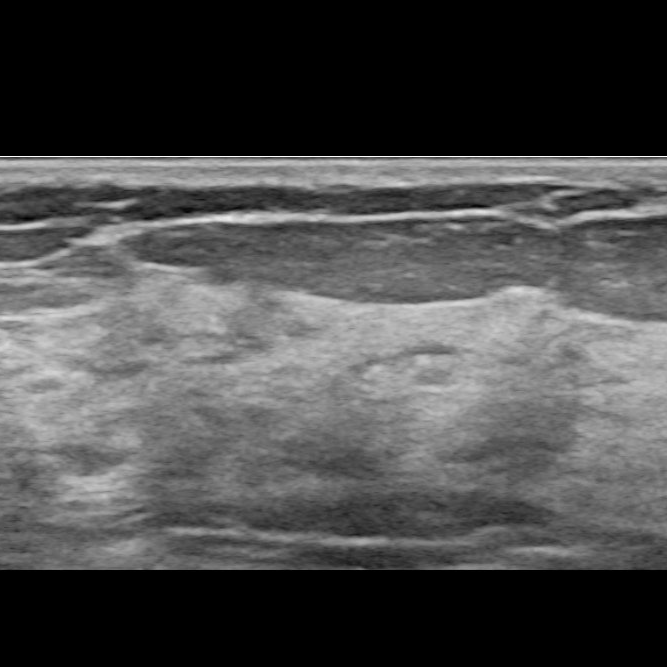

Zyste: Durch eine Kapsel abgeschlossener gutartiger Tumor mit flüssigem Inhalt